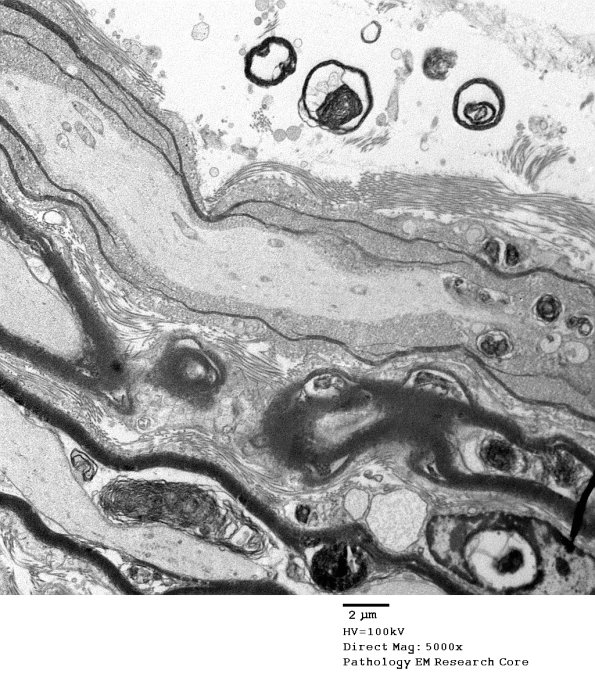

Washington University Experience | PERIPHERAL NEUROPATHY | 0 PNS ARTIFACTS | 19C1 Artifact, vesicular myelin, spinal root EM 021A - Copy

19C1-3 There is a similar abnormality extending along this longitudinally oriented axon. (electron micrograph)